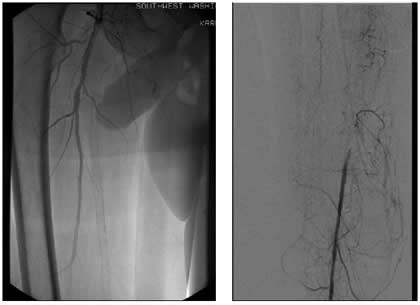

Case 3: An 81-year-old male with rest pain. The patient underwent angiography via an antegrade approach, which revealed extensive

![]() |

| Figure 3A |

| Figure 3B |

| Figure 3C |

calcific lesions of the superficial femoral artery (Figure 3A) and a lesion in the tibio-peroneal trunk (Figure 3B). The SFA lesions were debulked with a laser and the patency restored with Viabahn stents (Figure 3C). The tibio-peroneal represented the sole run off and was left as we were worried about creating a disaster if the lesion ruptured or dissected. ABI increase from 0.19 pre-procedure to 0.55 post and the patient is now able to ambulate with manageable claudication. Options to treat the more distal lesion could involve using a distal protection device and coronary balloons and/or stents.